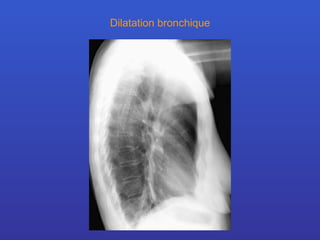

Dilatation bronchique